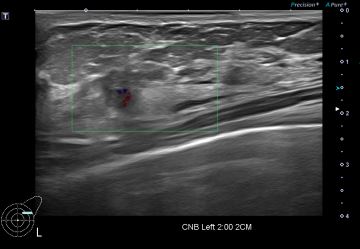

상기환자 외부 건강검진상 유방의 이상소견으로 정밀검사위해 내원하신 40대 여성분으로

좌측유방 혹 총조직검사 시행해 유방암 진단되었습니다